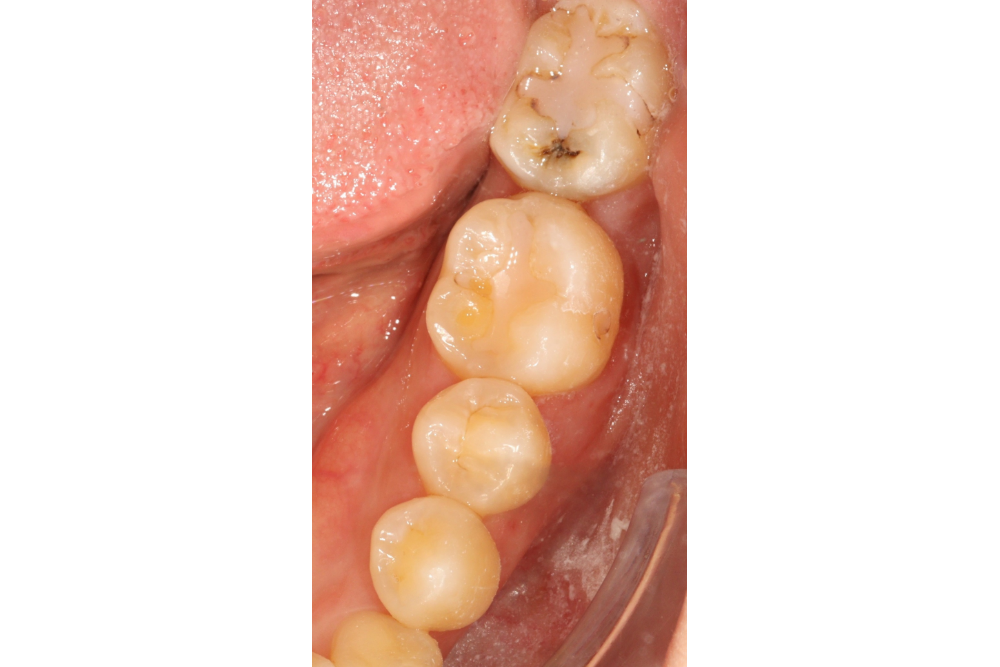

아래쪽 두 번째 어금니(제2대구치)가 선천적으로 없는 결손치로서, 사랑니(제3대구치)가 있으나 앞으로 쓰러져서 잘 안 씹히고 썩어 있습니다.

이런 경우 사랑니를 발치하고 임플란트를 하는 방법도 있으나, 본인 치아를 살리고 싶어하셔서 교정으로 접근하였습니다.

(본원은 교정과 임플란트 모두 다루므로 각 방법의 장단점을 충분히 비교 설명드렸습니다)

부분교정을 통해 누워있던 사랑니를 세웠으나, 씹는 면에 충치가 있습니다.

교정종료 후 보철치료(인레이)를 통해 씹는 기능을 회복시켰습니다.

누워있던 이가 세워져서 음식물이 더 잘 씹히게 되었습니다.

또한 음식물이 끼지 않게 되어 구강위생관리도 원활하게 되었습니다.